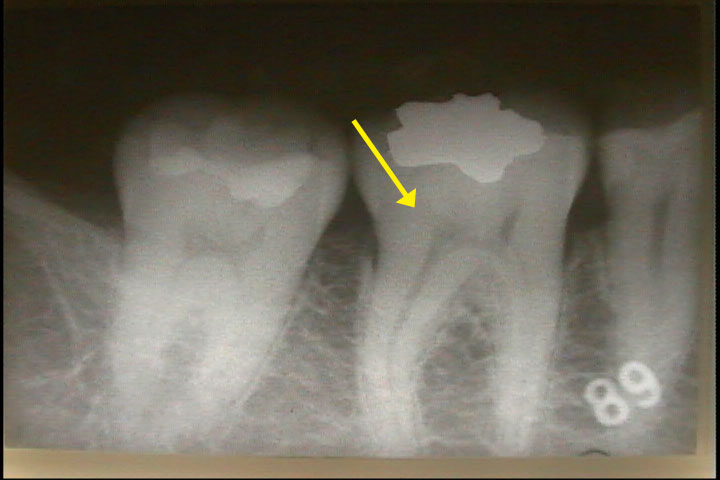

さて、問題の「むし歯」の原因を捜すために基本検査の視診「Photo-3」やレントゲン検査

「Photo-4」を行ないます。

症状は軽微、しかも充填物の辺縁封鎖は完全です。しかし、レントゲンの画像情報からは軽度の「むし歯」の存在が疑われる程度です。これでは前医2名が金インレーを除去せず要観察の判断も無理からぬ事です。しかし、これでは痛みの原因が不明のままになります。原因を解明するためには金インレーを除去する必要がありますが決断すべき決定的な根拠が不足しています。これが今までの検査法の限界です。

そこで問題の歯の周囲をレーザー光で走査(スキャンニング)させることにより象牙質の微細な崩壊部やクラック(ひび割れ)を検査致します。その結果、充填物の下方に深い「むし歯」を示す「99」(Photo-5)の数字が表示されました。レントゲンの推定位置と合致しますので充填物を除去します。従来の検査法では、このような充填物直下の微細な「むし歯」やクラックを検出することは困難でした。